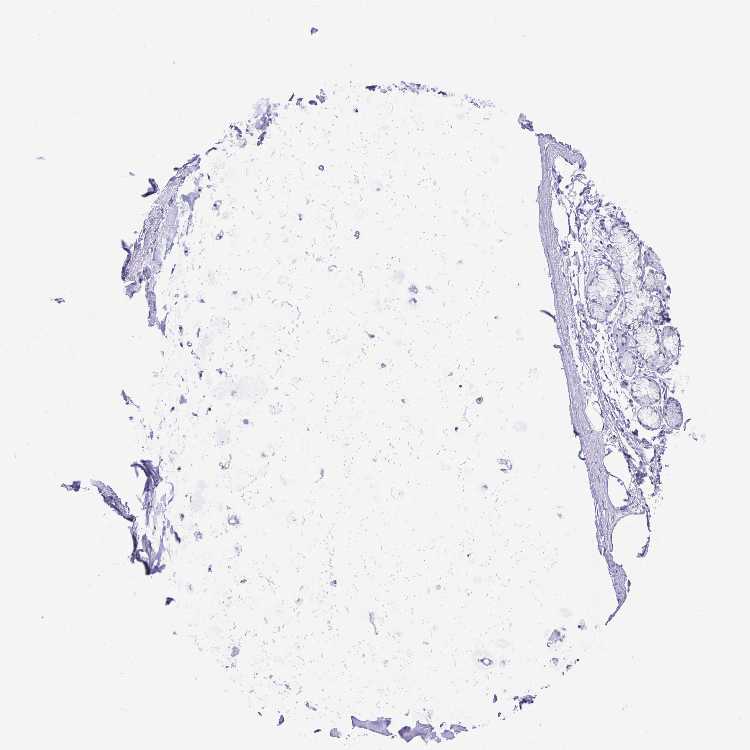

SOFT TISSUE 1 - Antibody stainingi

Antibody staining in the annotated cell types in the current human tissue is reported as not detected, low, medium, or high, based on conventional immunohistochemistry profiling in selected tissues. This score is based on the combination of the staining intensity and fraction of stained cells.

Each image is clickable and will lead to virtual microscopy that enables deeper exploration of all samples and also displays staining intensity scores, fraction scores and subcellular localization as well as patient and tissue information for each sample.

Antibody HPA021836Antibody HPA052215Antibody CAB025197

Chondrocytes -Not detected-

Fibroblasts Not detectedNot detectedNot detected

Peripheral nerve Not detectedNot detectedNot detected